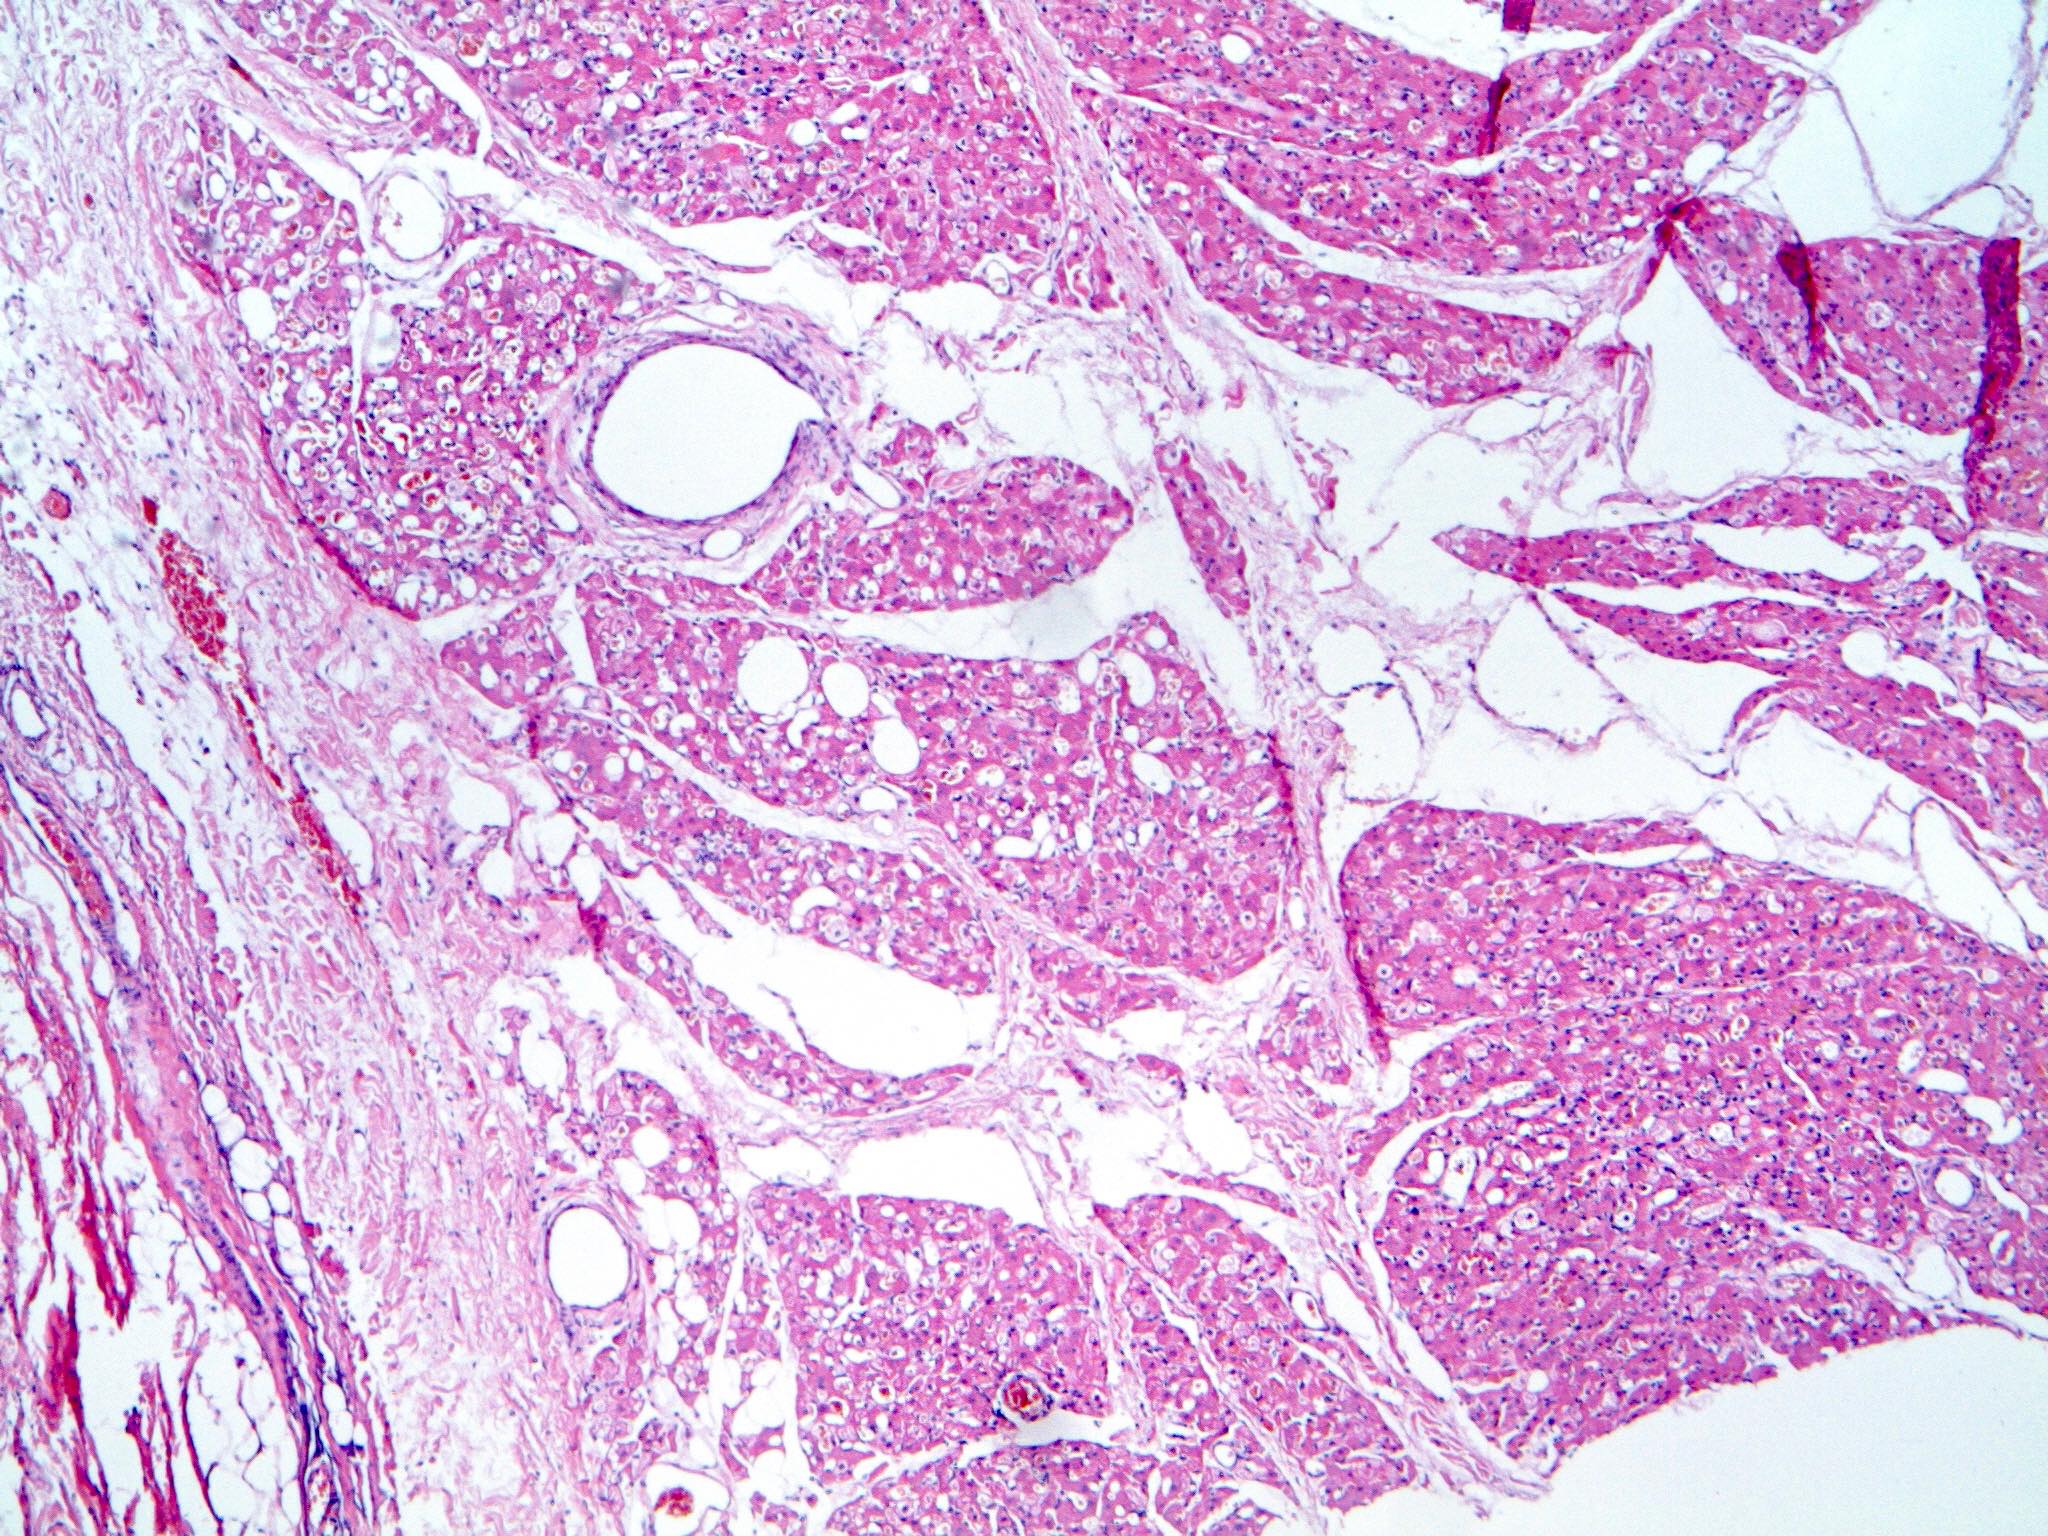

Microscopic (histologic) description

- Neoplastic lesion composed of polygonal brown fat cells with stromal cells in the background (Case Rep Oncol 2017;10:438)

- Large number of pale and eosinophilic brown fat cells with multivacuolated, eosinophilic granular cytoplasm and small central nucleus (about 70%) admixed with variable amount of univacuolated white cells (Case Rep Oncol 2017;10:438, Am J Case Rep 2020;21:e921447, J Comput Assist Tomogr 2019;43:793, J Pathol Transl Med 2017;51:499, Am J Surg Pathol 2018;42:951, Virchows Arch 2021;478:527)

- Multivacuolations resemble lipoblasts

- Morphological variations or subtypes: typical, myxoid (9%), lipoma-like (7%), spindle cell (2%), thick bundles of collagen fibers, presence of mast cells and exclusively containing brown fat cells (Case Rep Oncol 2017;10:438, Am J Case Rep 2020;21:e921447, Virchows Arch 2021;478:527)

- Cytological atypia, necrosis and mitosis is unusual (J Pathol Transl Med 2017;51:499, Am J Surg Pathol 2018;42:951, BMC Surg 2021;21:30)

Microscopic (histologic) images